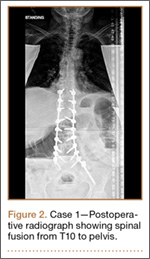

Operative Procedure. The patient underwent transpsoas lumbar interbody fusion (XLIF, NuVasive) from L1 to L4 and posterior spinal fusion from T10 to pelvis (Expedium, Depuy Synthes) (Figure 2). Operative time was 553 minutes; estimated blood loss was 2000 mL due to intraoperative coagulopathy (platelets, 40,000/µL) near the end of the posterior portion of the procedure. Intraoperative hypotension was treated by volume resuscitation and transient use of vasopressor agents. She was transfused with 1700 mL of blood, 150 mL of saline solution, and 420 mL of Lactated Ringer’s solution. No intraoperative complications occurred. The patient was extubated uneventfully on postoperative day 1 and was at baseline neurologically with no visual disturbances.